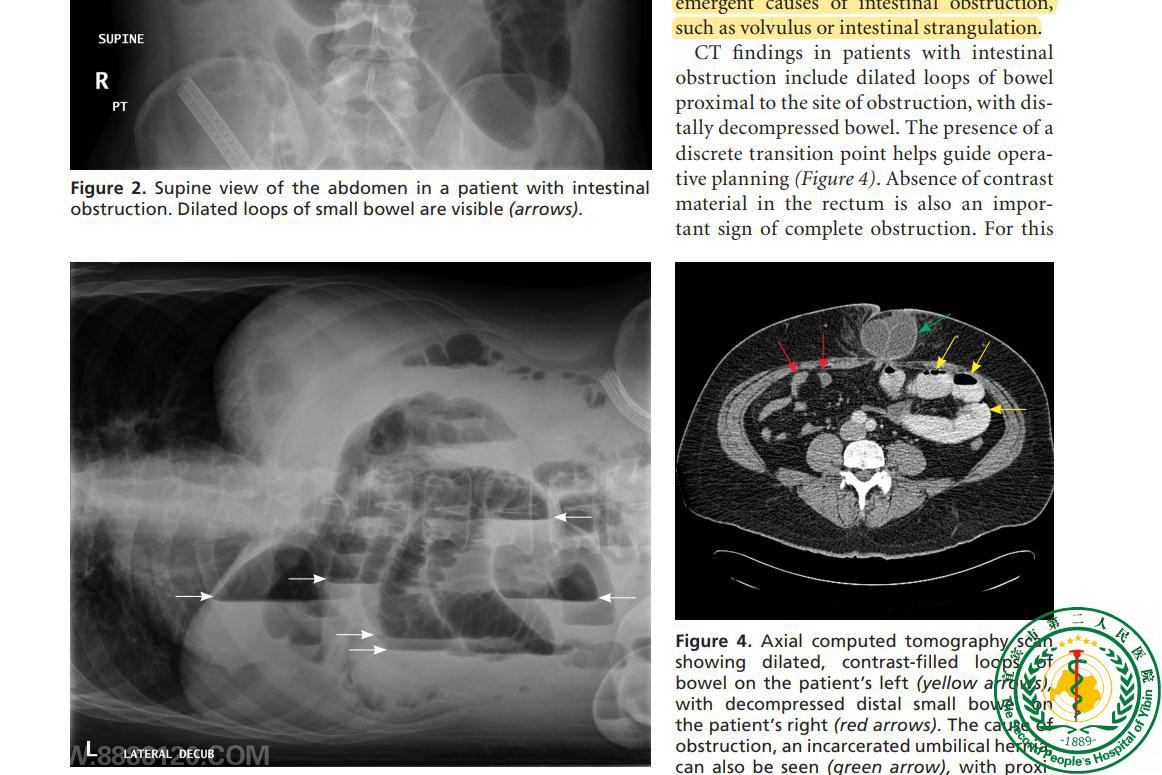

Evaluation and Management of Intestinal Obstruction